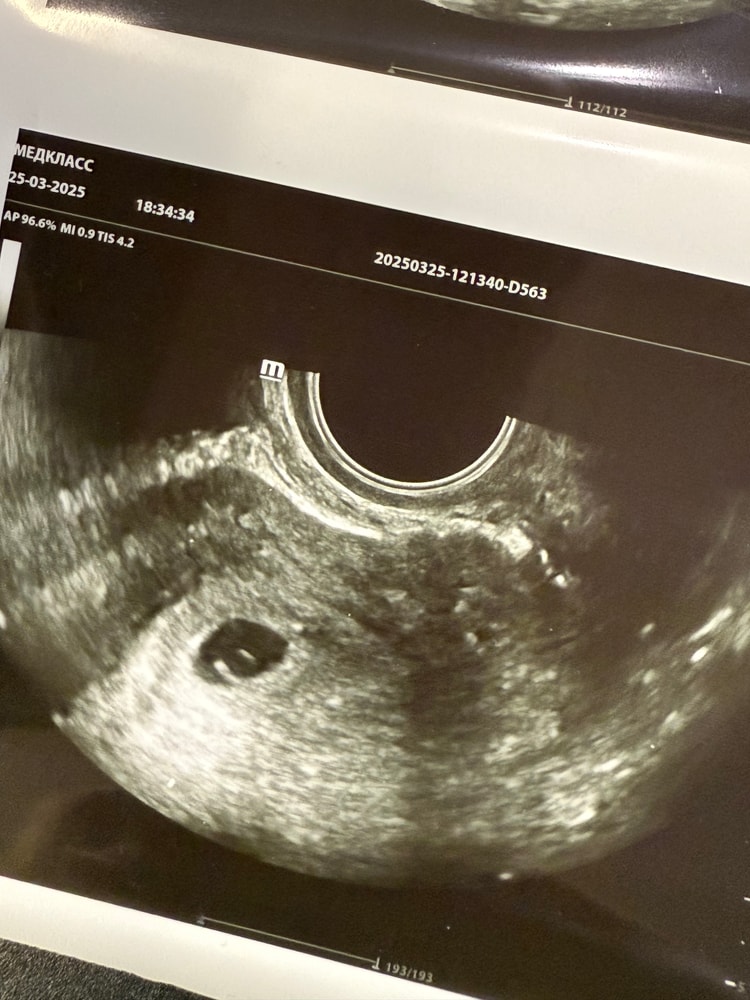

Ledi в Зачатие 8 месяцев УЗИ 5недель5 дней💍🫶🏼🥹🥰 УЗИ Только приехали с УЗИ, наконец-то посмотрели на нашу крошечку🤗всё соответствует сроку 5-6 недель, ПЯ-11мм, начинает просматриваться эмбрион 3мм, сердечко ещё формируется,через пару недель можно будет послушать 🙏🏻Расти, наша крошка🥰 Посмотрите еще 20 записей на эту тему Отменить Ответить Дарина Пусть крошка растет! Поздравляю! 25.03.2025 Ответить Ledi Дарина , спасибо! И вам расти здоровенькими😉🙏🏻 25.03.2025 Ответить Зачатие Мазня на 4 неделе Чаты Беременных Выберите чат: Январята-2026 Февралята-2026 Мартята-2026 Апрелята-2026 Майчата-2026 Июнята-2026 Июлята-2026 Августята-2026